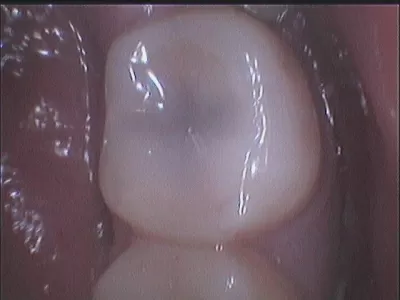

Галерея

15